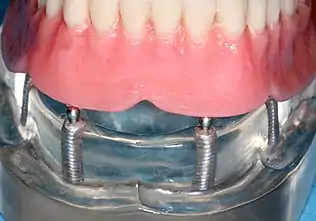

Four mandibular implants

Four lower implants to retain a complete denture with novaloc abutments

lower denture implant housing

Underside of a denture; housing fits like a ball and socket to hold the denture

Panorex radiograph showing implants

Xray of four Straumann implants and abutments

When a removable denture is worn, retainers to hold the denture in place can be either custom made or "off-the-shelf" (stock) abutments. When custom retainers are used, four or more implant fixtures are placed and an impression of the implants is taken and a dental lab creates a custom metal bar with attachments to hold the denture in place. Significant retention can be created with multiple attachments and the use of semi-precision attachments (such as a small diameter pin that pushes through the denture and into the bar) which allows for little or no movement in the denture, but it remains removable.[17]:33–34 However, the same four implants angled in such a way to distribute occlusal forces may be able to safely hold a fixed denture in place with comparable costs and number of procedures giving the denture wearer a fixed solution.[54]

Alternatively, stock abutments are used to retain dentures using a male-adapter attached to the implant and a female adapter in the denture. Two common types of adapters are the ball-and-socket style retainer and the button-style adapter. These types of stock abutments allow movement of the denture, but enough retention to improve the quality of life for denture wearers, compared to conventional dentures.[55] Regardless of the type of adapter, the female portion of the adapter that is housed in the denture will require periodic replacement, however the number and adapter type does not seem to affect patient satisfaction with the prosthetic for various removable alternatives.[56]